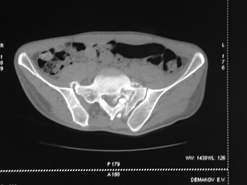

Диагноз : Сочетанная травма. ЗЧМТ. Перелом свода черепа. Ушиб головного мозга.Разрыв лонного и крестцово-подвздошного сочленений с нарушением целостности тазового кольца, с массивной забрюшинной гематомой и пропотеванием в брюшную полость. Перелом 10 ребра справа, осложненный гемопневмотораксом справа, правосторонней пневмонией на фоне ушиба правого легкого. Шок 3-4 ст. Больной поступил в отделение 07.03.2005г. в 16.00 в экстренном порядке через 30 минут после автодорожной травмы.Доставлен КСП. При поступлении состояние больного крайне тяжелое, явления травматического шока, А/Д-80/60 мм.рт. ст. ЧСС-120.В экстренном порядке поднят в операционную, интубирован, совместно с диагностическими мероприятиями лечение шока.При осмотре выявлены перелом 10 ребра справа, разрыв лонного и правого крестцово-подвздошного сочленений. Имеется линейный перелом теменной и височной костей слева с переходом на основание. Диагностическая лапароскопия 07.03.2005г. в 16.30-массивная забрюшинная гематома малого таза.Оставлена контрольная, дренажная трубка.Учитывая кровь в моче произведена цистография - данных за разрыв мочевого пузыря не найдено. Больной переведен в реанимационное отделение.За 08.03.2005г. из брюшной полости выделилось до 1500,0 мл, крови, часть крови реинфузирована. 08.03. в 06.30 наложен торокоцентез справа,удалено 100,0 мл. крови и 200,0 мл. воздуха .. Учитывая продолжающеееся кровотечение в брюшную полость из перелома костей таза, для исключения возможного разрыва внутренних органов 09.03.2005г. произведена Видеолапароскопия., на которой повреждения органов брюшной полости не выявлено.Одновременно произведен шов лонного сочленения проволокой и винтами, с одномоментным наложением стержневого аппарата на кости таза, с целью уменьшения кровотечения из разрывов тазовых сочленений, дренирование гематом. В последующем состояние больного оставалось тяжелым. 10.03.наложена нижняя трахеостома.Далее неоднократно производилась лечебно-диагностическая ФБС.С 10.03 выявлена правосторонняя плевропневмония. КТ головного мозга от 10.03-субарахноидальноекровоизлияние.Срединные структуры не смещены. КТ-контроль от 15.03-открытая моновентрикулярная гидроцефалия4 желудочка. Полисинусит. Постепенно состояние больного медленно прогрессировало к улучшению.С 24.03 переведен на самостоятельное дыхание, а 09.03 переведен в травматологическое отделение.Аппарат стержневой снят из-за перелома стержня (раскрутил больной самостоятельно).После госпитализации в наше отделение проведено дополнительное обследование Рентгекнография, КТ.Хотелось бы услышать Ваше мнение о дальнейшей тактике.-- С уважением, Leonid

Углядел билатеральное повреждение таза. Имеется вертикальная нестабильность со стороны перелома боковой массы крестца, ротационная с контрлатеральной стороны - чрезподвздошный разрыв кп сочленения. Разрыв лона, запирательные отверстия вроде целы.

DS. на сегодняшний день: Вертикальная двусторонняя нестабильная деформация таза, неправильно срастающийся перелом боковой массы крестца слева, срастающийся перелом крыла правой подвздошной кости, застарелый частичный разрыв правого кп сочленения, застарелый разрыв лонного сочленения.